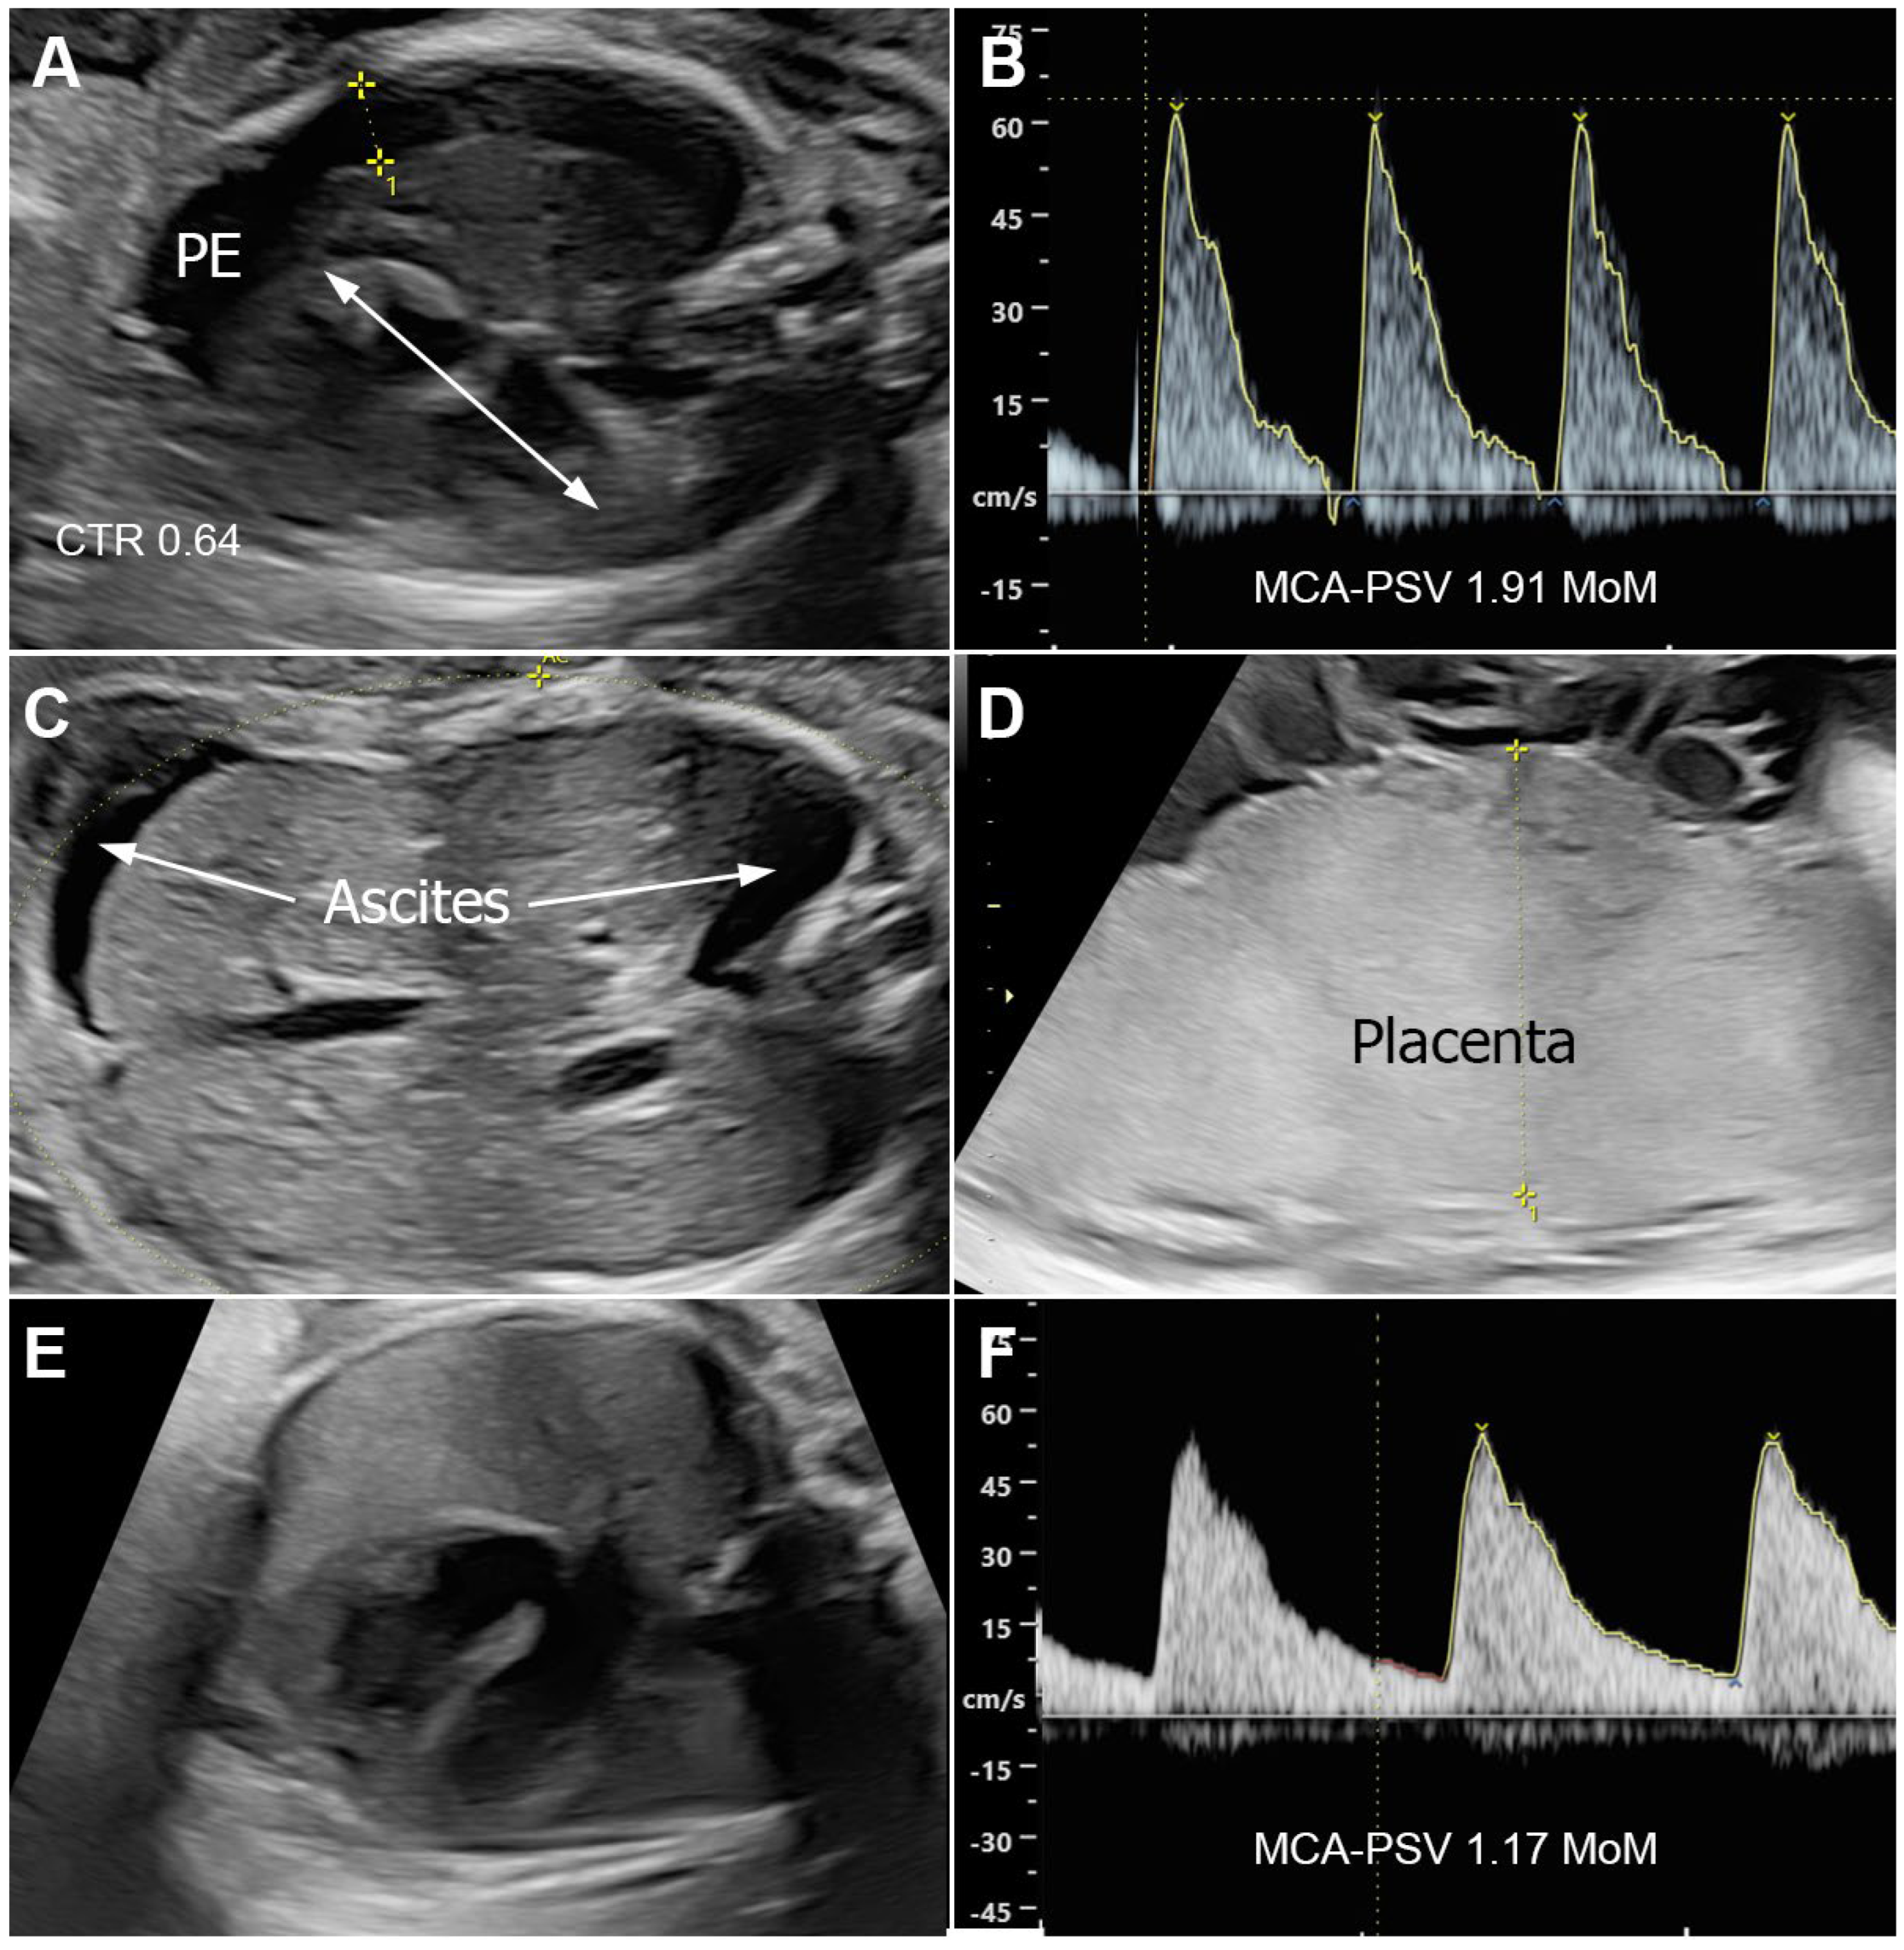

Fetal ultrasound examination revealed biometry corresponding to 26 weeks of gestation. However, the fetus exhibited ascites, right-sided pleural effusion, and subcutaneous edema, leading to a diagnosis of hydrops fetalis (Figure 1A–D). There was evidence of placentomegaly or cardiomegaly, no structural abnormalities, and no tricuspid regurgitation. The middle cerebral artery peak systolic velocity (MCA-PSV) was 64.8 cm/s (1.91 MoM). Doppler studies of the umbilical artery, umbilical vein, and ductus venosus were normal. No other structural anomalies were observed. Other potential causes of hydrops fetalis were not identified, and a provisional diagnosis of hydrops fetalis secondary to syphilis was made. Cordocentesis for fetal anemia evaluation and potential intrauterine transfusion was offered. However, the patient and her husband opted for close monitoring with serial MCA-PSV assessments rather than an invasive procedure. The patient received intramuscular benzathine penicillin G (2.4 million units) once weekly for three weeks. A follow-up ultrasound four days later showed no significant change in hydropic signs or MCA-PSV. By 28 weeks of gestation, ascites and pleural effusion had subjectively improved. By 33 weeks, all hydropic signs had resolved and were not observed in subsequent biweekly follow-up ultrasounds and MCA-PSV had decreased to 54.5 cm/s (1.31 MoM) (Figure 1E,F). Non-stress tests remained reactive throughout the third trimester. At 38 weeks of gestation, the patient experienced spontaneous labor and underwent vaginal delivery, giving birth to a healthy female newborn weighing 2850 g, with Apgar scores of 8 and 10 at 1 and 5 min, respectively. All neonatal workup results were within normal limits, with no signs of congenital syphilis. The newborn was treated with aqueous crystalline penicillin G at a dose of 143,000 units intravenously every 12 h from days 1 to 7, followed by 143,000 units intravenously every 8 h from days 8 to 10 (50,000 units/kg/dose). The infant remained healthy, with normal findings at the 2-month follow-up.

Figure 1. Ultrasound findings of Case 6; (AD) (26 weeks) show hydrops; pleural effusion (PE) and cardiomegaly (A), high MCA–PSV (B), ascites (C), and placentomegaly (D); (E,F) (33 weeks) show disappearance of hydrops; no pleural effusion (E) and normal MCA–PSV (F).